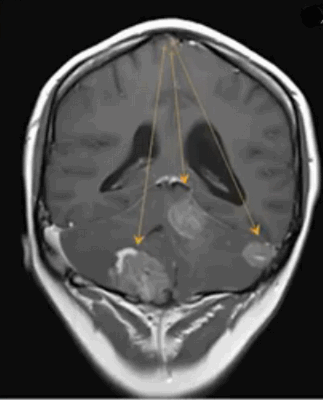

Метастазы в головном мозге на постконтрастном изображении (указаны стрелками)

Множественные метастазы в вещество головного мозга на МРТ без контраста

Вторичными проявлениями патологии могут быть:

- латеральная дислокация срединных структур;

- смещение сосудистого пучка;

- изменение величины и деформации желудочков;

- аксиальная дислокация;

- окклюзионная гидроцефалия при блокаде ликворных путей;

- смещение или деформация базальных цистерн;

- отек мозга в зоне опухоли и вокруг нее (локальный, генерализованный, тотальный, перивентрикулярный).

- метастазы. Выглядят, как множественные образования в тканях головного мозга различных размеров, неправильной формы, с неровными контурами, накапливающие контраст, с различной интенсивностью отека вокруг;